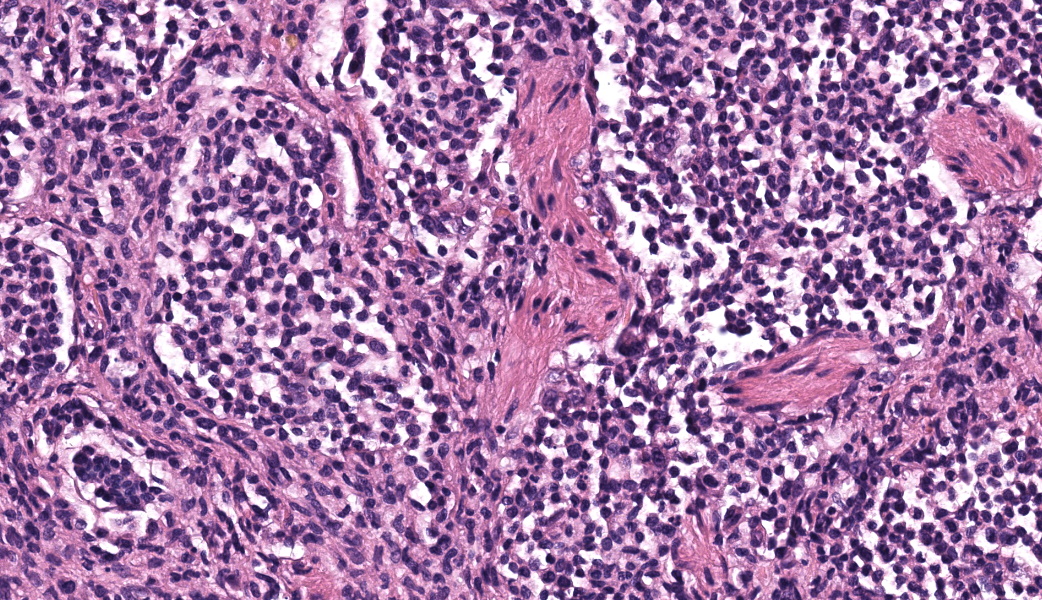

Expanding the airway and alveolar interstitium, subpleural spaces and also filling alveolar spaces, there is a proliferation of large numbers of round-polygonal cells. The proliferative round cell population have a moderate amount of eosinophilic cytoplasm and a reniform nucleus that contains coarsely stippled chromatin and a single nucleolus. There is mild anisocytosis and anisokaryosis, and there are occasional multinucleated cells. There is one mitotic figure per 2.37 square mm. Within the pleural, peribronchiolar interstitium and alveolar septa, the proliferative cells are accompanied by fine strands of collagen, resulting in further expansion of those structures, and in some areas, complete effacement of the normal pulmonary architecture with obliteration of air spaces. In non-consolidated areas, alveolar septa are multifocally ruptured (microscopic emphysema). There is multifocal, moderate, hyperplasia of bronchiolar smooth muscle, and occasionally, especially in subpleural areas, there is type 2 pneumocyte hyperplasia. Medium-sized pulmonary arteries demonstrate hyperplasia of the tunica media. Airway epithelium is frequently sloughed (post-mortem artefact). Gram, Ziehl-Neelson and PAS-stained sections do not highlight micro-organisms.Contributor's Morphologic Diagnoses:

Lung, feline pulmonary histiocytosisEtiological diagnosis: Feline pulmonary Langerhans cells histiocytosis

Typical microscopic findings include pleomorphic histiocytic cells that target terminal and respiratory bronchioles and extend into adjacent alveoli.3 Affected bronchioles undergo smooth muscle hyperplasia and there is fibrosis of the alveolar septa. The Langerhans cells demonstrate CD18 and E-cadherin, vimentin and IBA-1positive immunoreactivity.1 In addition, feline Langerhans cells do not react to CD204.7